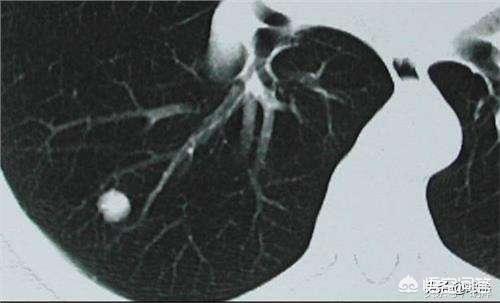

Les nodules pulmonaires sont classés en différents types en fonction de leur densité. Les nodules de densité plus élevée, qui apparaissent comme des points blancs sur le scanner thoracique, sont appelés nodules solides, tandis que les nodules en verre dépoli sont plus légers et ressemblent à de la vapeur d'eau sur le verre. Les nodules en verre dépoli, en particulier les nodules en verre dépoli pur, ont tendance à être plus malins.

Pour la définition du nodule pulmonaire, la directive médicale chinoise indique : L'imagerie (scanner thoracique) montre une ombre pulmonaire solide ou sous-solide focale, arrondie, de densité accrue, d'un diamètre ≤3 cm, qui peut être isolée ou multiple, et qui n'est pas accompagnée d'atélectasie pulmonaire, d'hypertrophie des ganglions lymphatiques hilaires et d'épanchement pleural.

D'une manière générale, toute ombre de densité accrue dans les poumons d'un diamètre inférieur à 3 cm est appelée nodule pulmonaire. Le degré de risque n'est pas seulement lié à la taille, mais doit également être déterminé en fonction de la morphologie, de la densité et de la vitesse de multiplication du nodule.